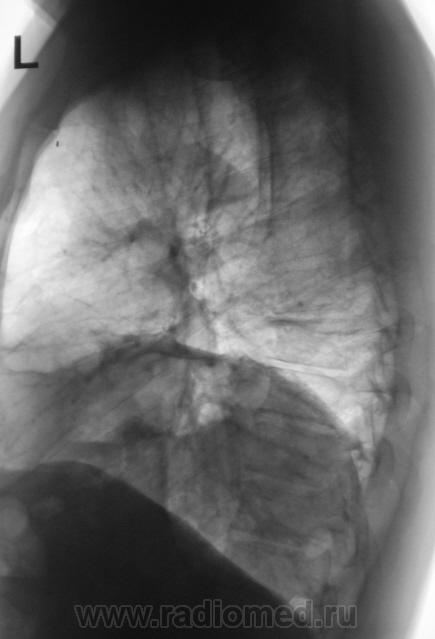

Рентгенограммы были сделаны в ургентном порядке, так как при поступлении, терапевта смутила стето-аускультативная картина слева.

Хотя, как выяснилось, жалоб пациент не предъявлял. Формальный диагноз при направлении на исследование -"Левосторонняя нижнедолевая пневмония". Произведена стандартная рентгенография в двух проекциях (без врача).

Возник извечный вопрос - пневмония, ателектаз, базальный плеврит.